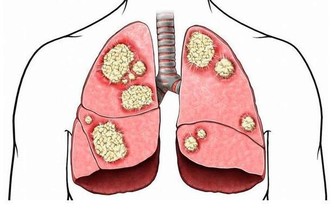

現在很多的年輕男性為了工作常應付多種應酬,在應酬中會經常大量的吸菸喝酒,長期吸菸對肺部會造成嚴重的損傷,容易誘發肺炎。所以經常吸菸的男性應該最好是戒菸,如一時戒不了煙,平時應該多吃一些能夠清肺的食物來保養肺部。

動物的肝臟和海藻以及蝦類食物,這些食物含有豐富的硒元素,因為吸菸會導致人體血液中的鋅元素偏低,但是硒元素是防而曠而不可缺少的一種微量元素,所以在平時應該多吃這類食物,能起到抗癌防癌的作用。

有研究發現,堅果類食物和粗糧等含維生素e豐富的食物,可以降低吸菸者得肺癌的幾率。